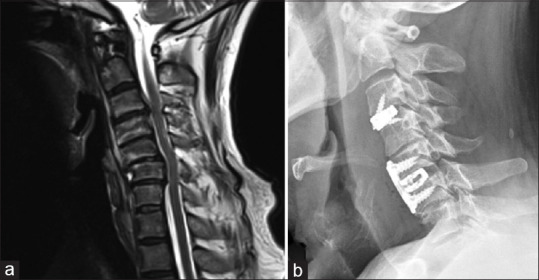

Methods: Fifty-two patients who underwent management of NCDDD and two-level contigious disc disease (CDD) over 6 years from 2014 to 2020 were included in the study. There were 44 male and 8 female patients with a mean age of 46.75 years. These patients were divided into two groups: Those who underwent contiguous discectomy and those who underwent skip discectomy with either anterior cervical discectomy (ACD) alone, ACD and fusion (ACDF), or ACDF with plating based on individual pathology and surgeon preference. Outcomes were assessed using clinical parameters such as modified Japanese Orthopaedic Association Score (mJOAS) and Nurick grade and radiological parameters such as disc height improvement, spinal alignment change, and fusion rates.

Results: The overall mean duration of follow-up was 15.23 ± 23.69 months, with a clinical follow-up period of 23.87 ± 21.51 months and a radiological follow-up period of 7.57 ± 5.91 months, with follow-up in Group 1 being 24.67 ± 23.17 months and in Group 2 being 20.03 ± 10.53 months. The mean blood loss in Group 1 was 200.47 mL; in Group 2, it was 172 mL. The preoperative mJOAS was 10.19 ± 3.16, and the postoperative mJOAS was 12.73 ± 2.92 (P = 0.001). Nurick grade showed improvement from a preoperative mean score of 4.23 ± 1.02-3.65 ± 0.88 postoperatively (P < 0.001). Statistically significant improvement in intervertebral height at superior and inferior levels was observed. Outcomes for Skip discectomy regarding mJOAS, Nurick grade, radiological parameters, fusion, and complication rates were noninferior to contiguous discectomy and fusion.

Conclusion: Skip discectomy has a similar benefit and risk profile and is noninferior compared to contiguous discectomy in addition to the preservation of intermediate disc integrity.